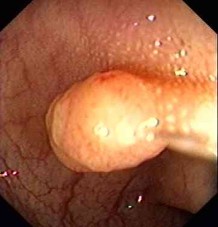

Vorsorge Darmspiegelung / diagnostische Darmspiegelung

Präventive Koloskopie (Vorsorge Darmspiegelung)

Darmpolypentfernung / ambulante Polypektomien

Diagnostische Koloskopie zur Abklärung abdomineller Beschwerden, ggf. mit Probeentnahmen (z.B. bei Verdacht auf chronisch-entzündl. Darmerkrankung)

Endoskopische Tumornachsorge